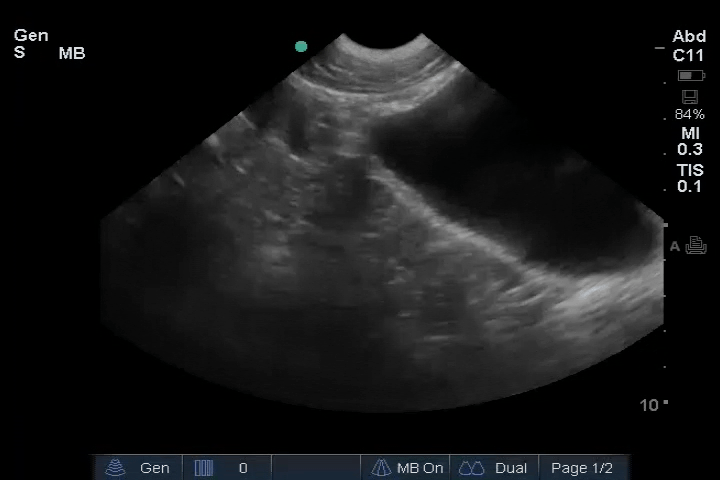

01_Lung_Ant_Right – B-lines